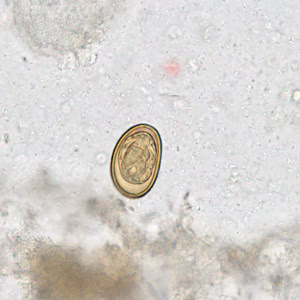

Dicrocoelium dendriticum eggs in wet mounts.

Diagnosis is based on microscopic identification of eggs in the stool, duodenal, and/or bile fluid. Note that eggs may be detected in stool following consumption of liver infected with adult flukes; additional specimens should be collected to distinguish this spurious passage from a true infection. Adult flukes are rarely recovered.